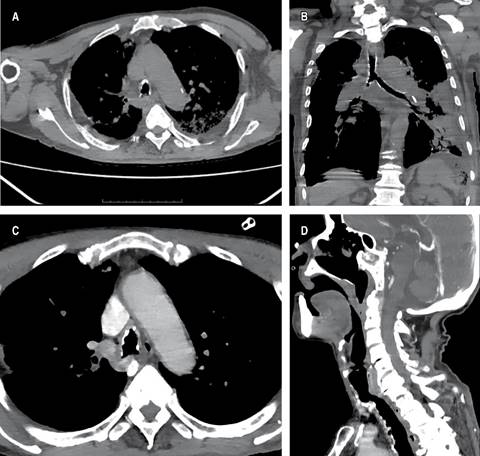

La tomografía de tórax (Figura 1) mostró opacidades reticulares intersticiales parahiliares bilaterales, más acentuadas en el campo pulmonar izquierdo, extendiéndose hacia los segmentos V, VIII, IX y X, con ocupación del espacio alveolar, aumento de la densidad del parénquima pulmonar y presencia de broncograma aéreo. Además, se identificó una lesión calcificada dependiente de la pared lateral a nivel de anillo traqueal 8, de aproximadamente 2 cm, que protruye hacia la luz traqueal.

Figura 1: A) Tomografía de tórax en corte axial con ventana de tejidos blandos en la cual se identifica lesión exofítica nodular con calcificación parcial localizada en la pared traqueal a nivel de C8 con compromiso parcial de la luz traqueal. B) Tomografía computarizada de tórax en corte coronal en ventana de tejidos blandos en la que se evidencia calcificación irregular de la pared traqueal hasta el bronquio principal con presencia de nodulaciones submucosas; se identifica, además, la consolidación basal izquierda con presencia de broncograma aéreo compatible con proceso neumónico. C) Tomografía computada de tórax contrastada en corte axial en ventana de tejidos blandos en la cual se identifica la imagen de nódulos calcificados en la pared traqueal anterior y lateral, de aspecto nodular con irregularidad en la superficie de la luz traqueal, respetando la pared posterior. D) Tomografía computada de tórax contrastada en corte sagital en ventana de tejidos blandos en la que se identifican protrusiones de las lesiones nodulares parcialmente calcificadas hacia la luz traqueal en la región anterior a nivel de C8 que generan estenosis de la misma, se observa la pared posterior completamente respetada sin lesiones en su superficie.